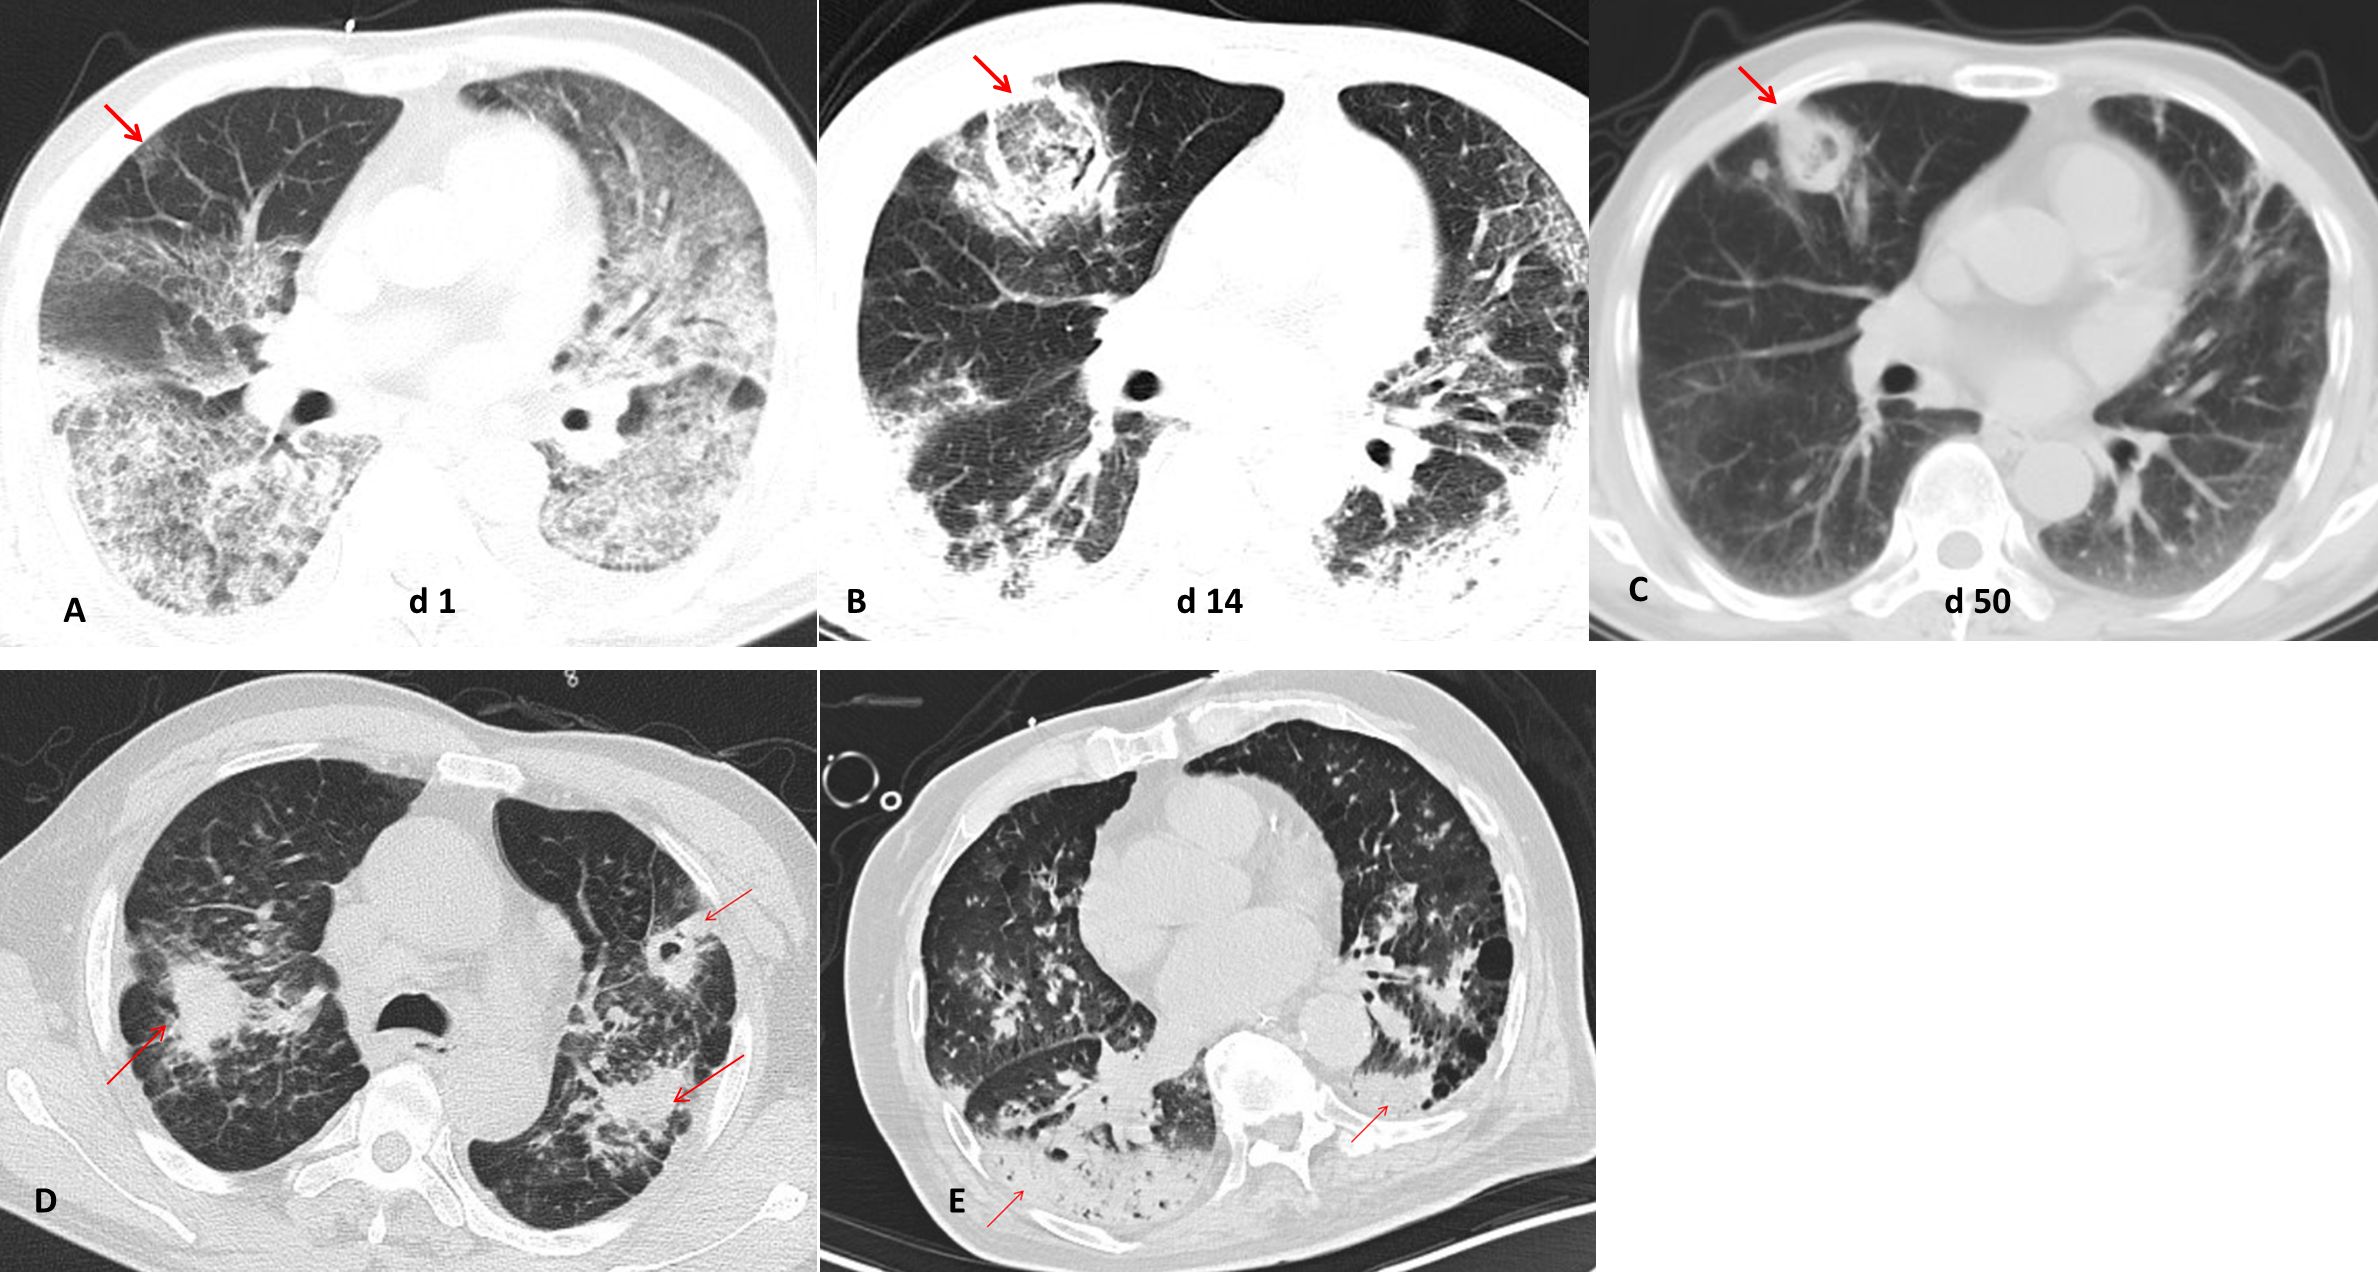

The chest CT characteristics of IAPA

IPA often appears as wedge-shaped lung consolidation, multiple small nodules, masses, and multiple small patches on chest CT scans, and the most distinctive features are wedge-shaped consolidation shadows and small nodular edges with “halo sign”. These radiographic features are frequently nonspecific and can change as the disease progresses (Alexander et al., 2021). In this study, there was no difference in the distribution of lung lobes (unilateral, bilateral) between IAPA patients and the control group. The number of nodules and cavities in the IAPA group was significantly higher than that in the Non-IAPA group, although there were also more halo signs in IAPA patients, the difference was not statistically significant (Table 2; Figure 1). It is worth noting that the lung imaging of the same IAPA patient may have different manifestations at different stages of the disease course. As shown in Figures 2A–C, an IAPA patient’s right lung lesion initially presented as ground glass opacities, then developed into subpleural wedge-shaped opacities, and later became solid nodular opacities. In addition, there may not be only one chest CT manifestation in the same IAPA patient, and multiple imaging forms often coexist, such as cavities and consolidation shadows (Figure 2D), consolidation shadows with or without inflation sign (Figure 2E). When influenza patients present with unexplained imaging manifestations of viral infection in the lungs, timely and comprehensive examinations should be conducted to determine whether there is IPA, in order to avoid missed diagnosis.

CT scans showing lung pathology over time. Image A (day 1) shows initial lung abnormalities with a red arrow pointing to affected areas. Image B (day 14) depicts increased opacification. Image C (day 50) shows a reduction in abnormal findings. Images D and E present lung conditions with several red arrows marking different affected areas, indicating persistent abnormalities.

Figure 2. Different chest CT imagings in IAPA patients. (A) An IAPA patient’s right lung lesion initially presented as ground glass opacities, (B) then developed into subpleural wedge-shaped opacities, (C) and later became solid nodular opacities. (D) Multiple chest CT imaging forms such as cavities and consolidation shadows coexist in one IAPA patient. (E) Consolidation shadows with or without inflation sign in chest CT imaging of one patient. The red arrow indicates the lesion.